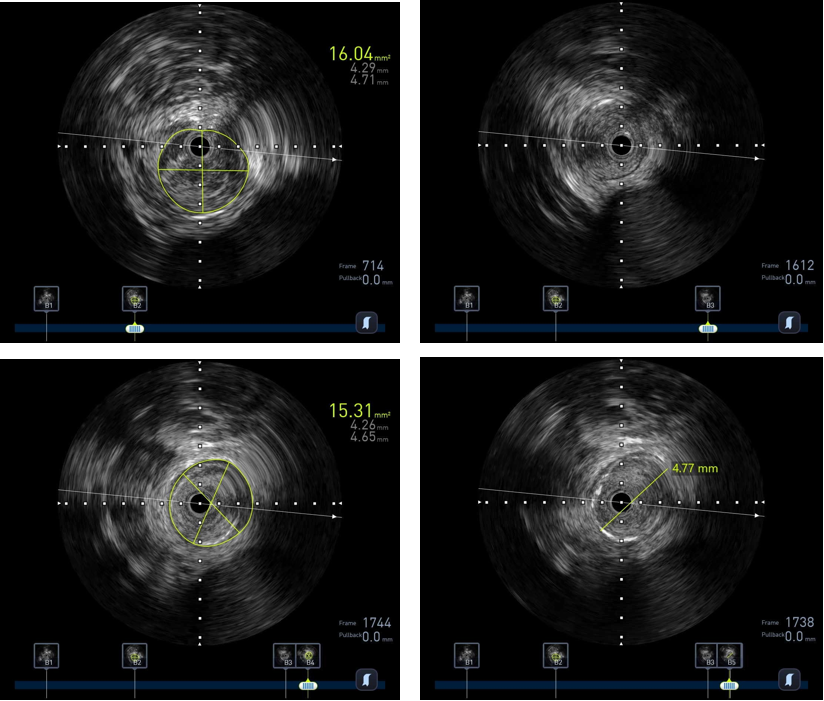

图:IVUS确认

图:IVUS测量